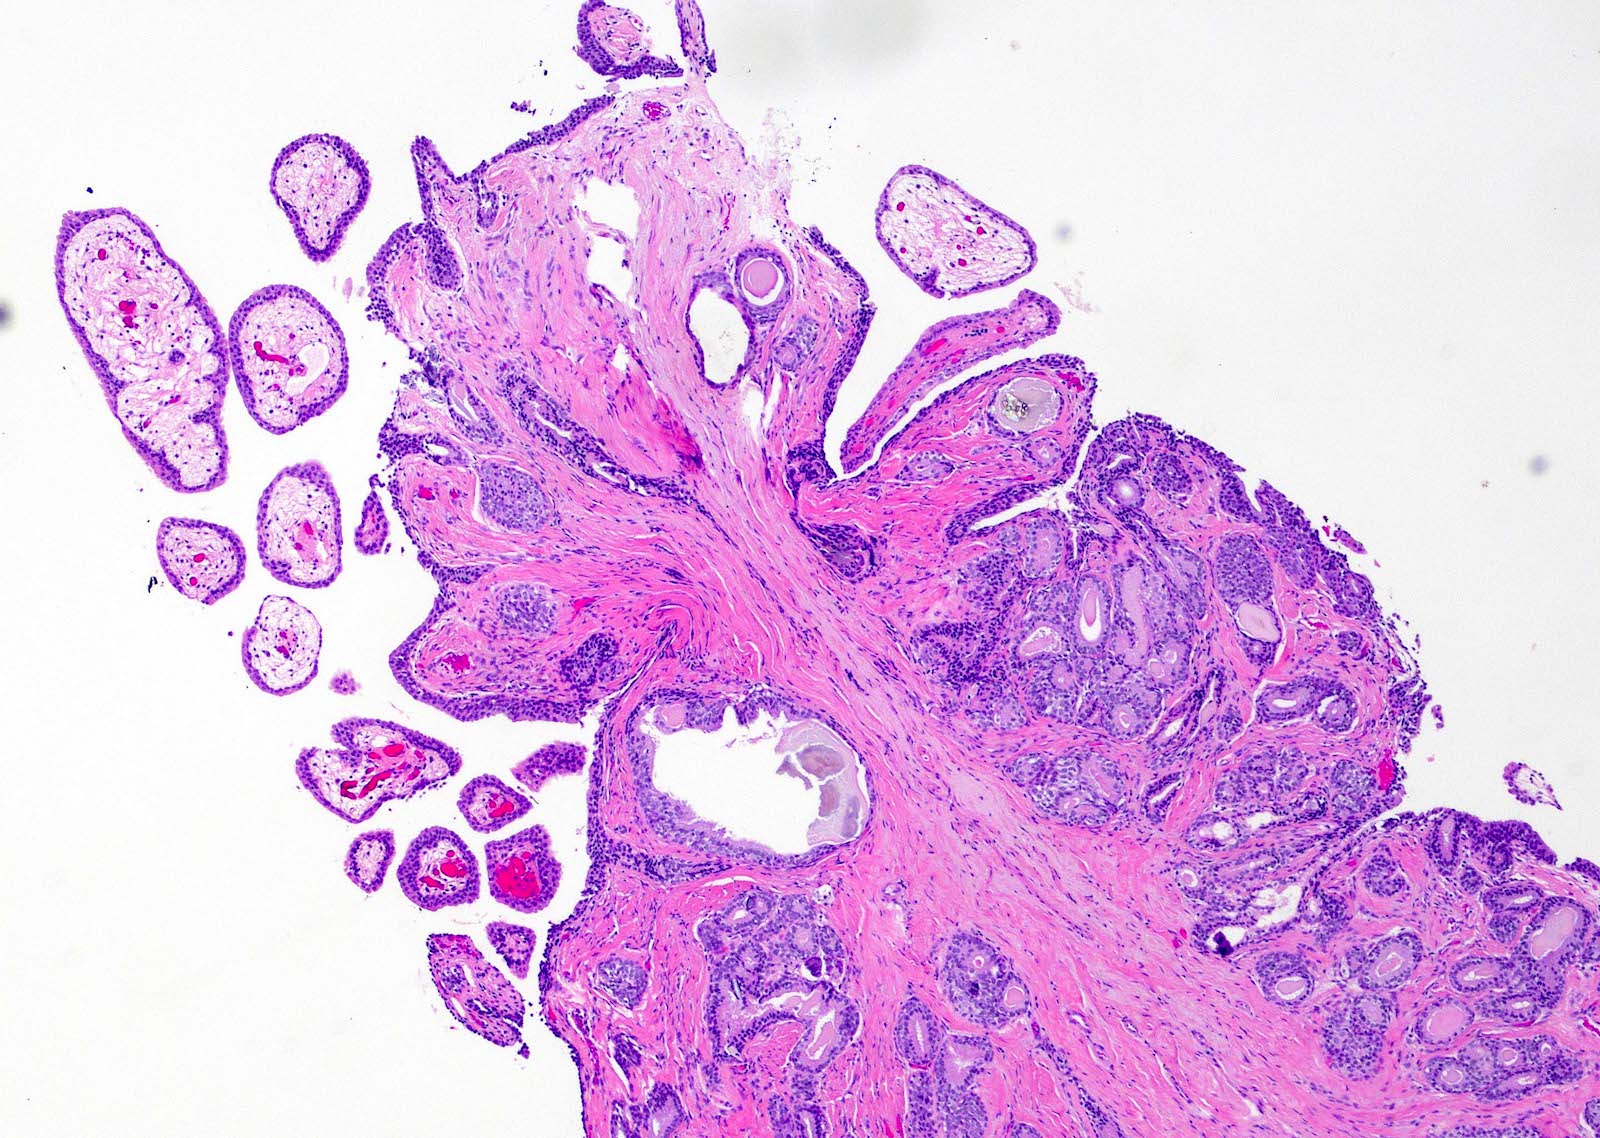

- Fibroepithelial urethral polyp (Am J Surg Pathol 2005;29:460):

- Pattern 1: most common pattern includes the following features

- Broad cloverleaf-like and club-like projections covered by normal urothelium and composed of dense fibrovascular stroma with florid cytitis cystica et glandularis (most common morphologic variant)

- Back to back glands present in the stalk

- Anastomosing nests of benign urothelial cells resembling inverted papilloma

- Dilated cysts with intracystic papillary contents

- Degenerative reactive atypia of stromal cells

Microscopic (histologic) images

Contributed by Y. Albert Yeh, M.D., Ph.D.

Fibroepithelial polyp